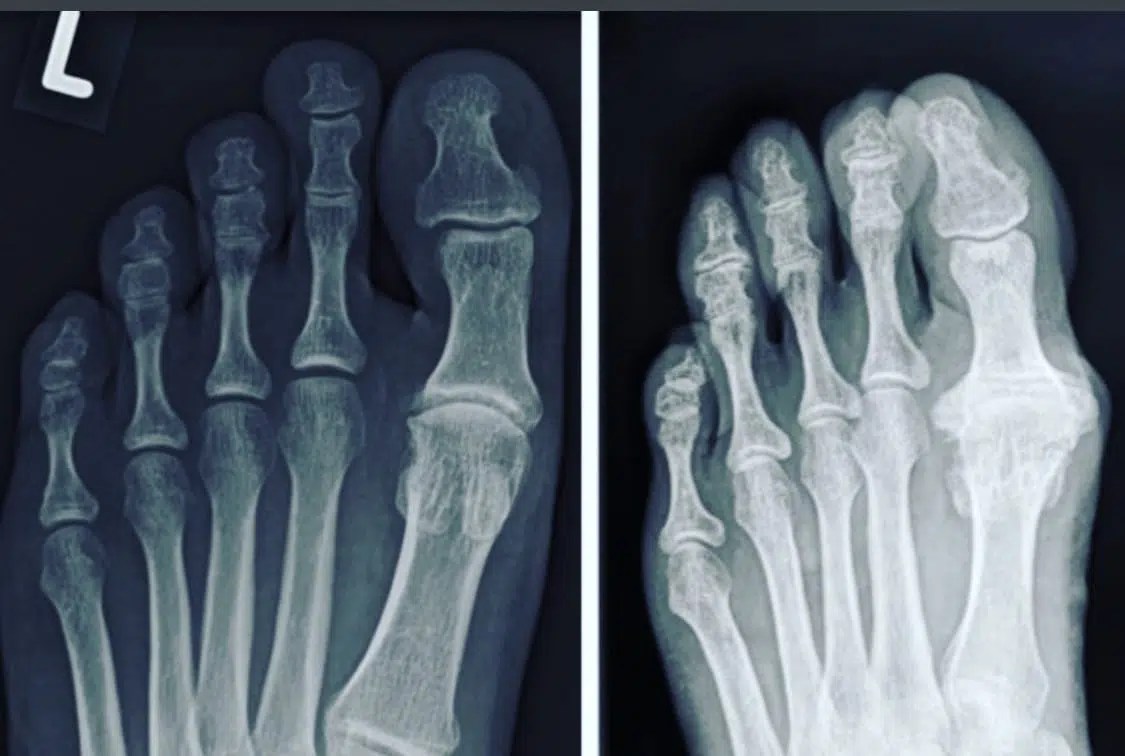

From ar.inspiredpencil.com

Hallux Rigidus X Ray Foot Hallux Rigidus It is one of the most. It is characterised by a complete absence of the joint's sagittal plane motion, specifically. Hallux rigidus (stiff big toe) occurs when the joint at the base of the big toe stiffens. It is the most common arthritic condition of the foot, affecting 1 in 40 people over the age of 50 and typically developing. Foot Hallux Rigidus.